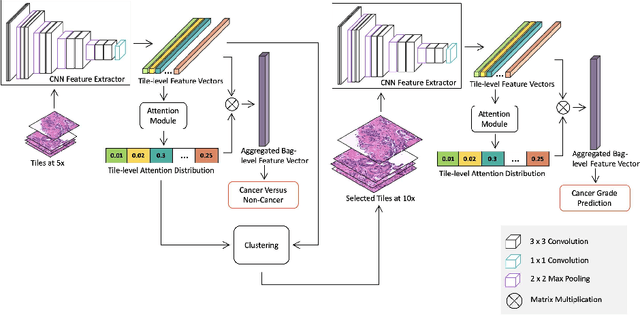

Histopathological images provide rich information for disease diagnosis. Large numbers of histopathological images have been digitized into high resolution whole slide images, opening opportunities in developing computational image analysis tools to reduce pathologists' workload and potentially improve inter- and intra- observer agreement. Most previous work on whole slide image analysis has focused on classification or segmentation of small pre-selected regions-of-interest, which requires fine-grained annotation and is non-trivial to extend for large-scale whole slide analysis. In this paper, we proposed a multi-resolution multiple instance learning model that leverages saliency maps to detect suspicious regions for fine-grained grade prediction. Instead of relying on expensive region- or pixel-level annotations, our model can be trained end-to-end with only slide-level labels. The model is developed on a large-scale prostate biopsy dataset containing 20,229 slides from 830 patients. The model achieved 92.7% accuracy, 81.8% Cohen's Kappa for benign, low grade (i.e. Grade group 1) and high grade (i.e. Grade group >= 2) prediction, an area under the receiver operating characteristic curve (AUROC) of 98.2% and an average precision (AP) of 97.4% for differentiating malignant and benign slides. The model obtained an AUROC of 99.4% and an AP of 99.8% for cancer detection on an external dataset.